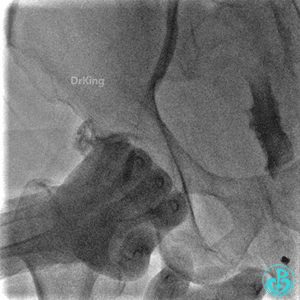

撤回逆向导丝及微导管造影,钝缘支远端侧支造影剂渗漏,局部造影剂滞留范围不断扩大。

明胶在血管怎么降解并发症丨前降支CTO同侧逆向开通时侧支血管破裂,弹簧圈联合明胶海绵封堵_https://www.jmylbn.com_新闻资讯_第31张

明胶在血管怎么降解并发症丨前降支CTO同侧逆向开通时侧支血管破裂,弹簧圈联合明胶海绵封堵_https://www.jmylbn.com_新闻资讯_第32张

前降支末梢经微导管释放3.0×2.5mm弹簧圈封堵破口。

明胶在血管怎么降解并发症丨前降支CTO同侧逆向开通时侧支血管破裂,弹簧圈联合明胶海绵封堵_https://www.jmylbn.com_新闻资讯_第33张

钝缘支经微导管释放5.0×5.5mm弹簧圈封堵破口。